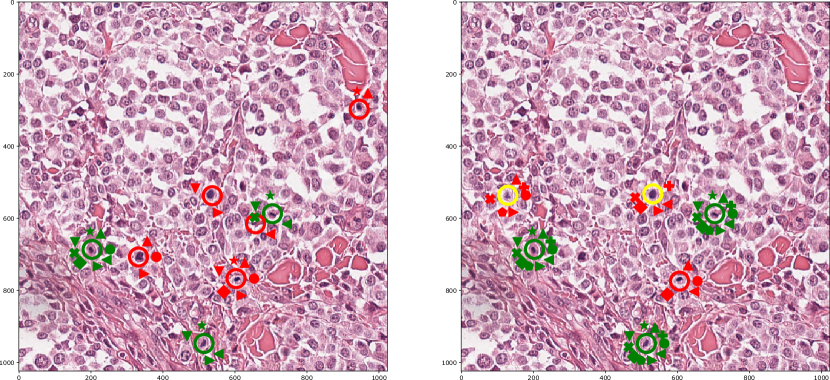

Figure 1: Examplary annotation results without (left) and with (right) algorithmic support. Green circles represent ground truth mitotic figures, red false-positives made by experts and yellow fake (artificially introduced) mitotic figures. A symbol at the corresponding annotation represents each expert.

Overall, we observed that the range of results in the computer-aided mode was reduced, resulting in higher comparability and repeatability of results, which is highly desirable in medicine. Furthermore, we were able to show that it was more likely that the experts overlooked artificially inserted errors (see Fig. 1). At the same time, our results indicate that the systematic errors did not lead to a deterioration of the trained classifier quality. This might be influenced by the artificial labelling errors being introduced symmetrically (i.e., the same number of mitotic figures added as removed), which might have inhibited the creation of an observable bias. Nonetheless, the overlooked artificially inserted errors are a particularly critical observation, as it shows that for all the advantages of speed and accuracy, the quality of the computer-aided annotation is crucial for the result and should be of the highest standard.